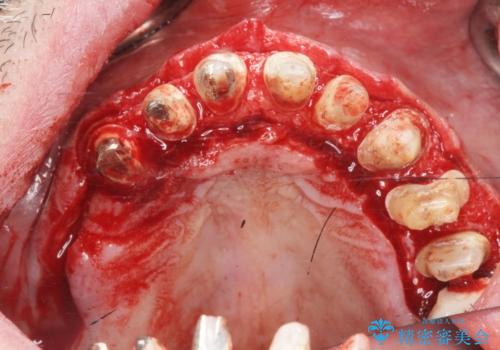

歯周外科を行い歯と歯槽骨・歯肉の関係を是正することで歯ぐきの状態を改善し、将来に亘り安定した歯周環境の維持を期待できるセラミック治療を実践します。

歯ぐきが腫れたままの状態だと、違和感が生じるとともに常に炎症が存在する環境となってしまうので非常に好ましくない口腔内環境です。